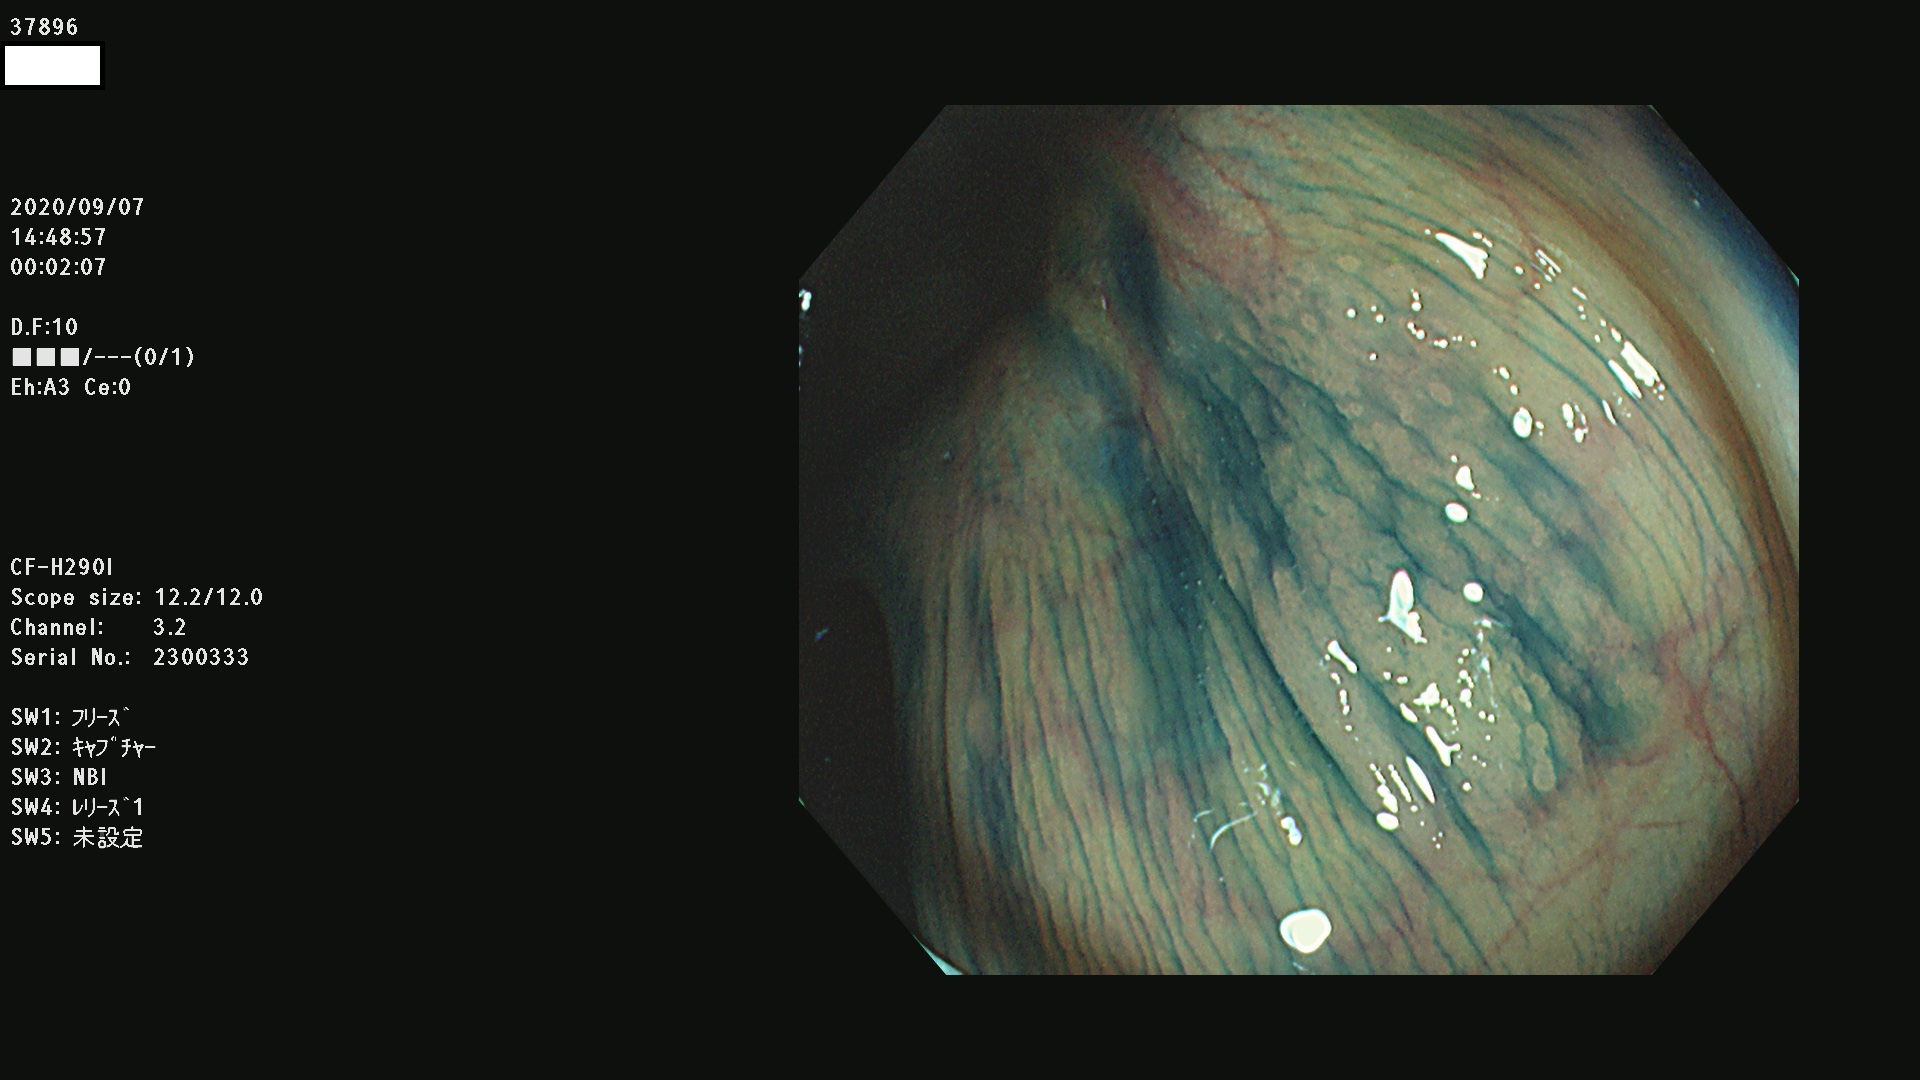

腺腫発見率 75 % (カルテ番号 37800〜37899の100名の方の検査結果で集計)大腸癌検診最新情報

以下のカルテ番号の方に腺腫(Adenoma,Group3〜5)が見つかりました(集計法)

37800(SSAPのみ) 37801 37802 37803 37804 37805 37806 37807 37808 37809(SSAPのみ) 37810 37811 37812 37813 37814 37815 37817 37818 37819 37820 37821 37822 37824 37825 37826 37827 37828 37829 37832 37833 37836 37837(SSAPのみ) 37839 37840 37842 37844 37845(SSAPのみ) 37847 37849 37850 37851 37852 37853(SSAPのみ) 37855 37856 37857 37860 37861 37862 37863 37864 37867 37868 37871 37874 37876 37877 37879 37880 37881 37882 37883 37886 37887 37888 37889 37890 37891 37892 37893 37894 37896 37897 37898 37899

発見困難で危険性の高い平坦型病変(上記100名より抽出) ![]()